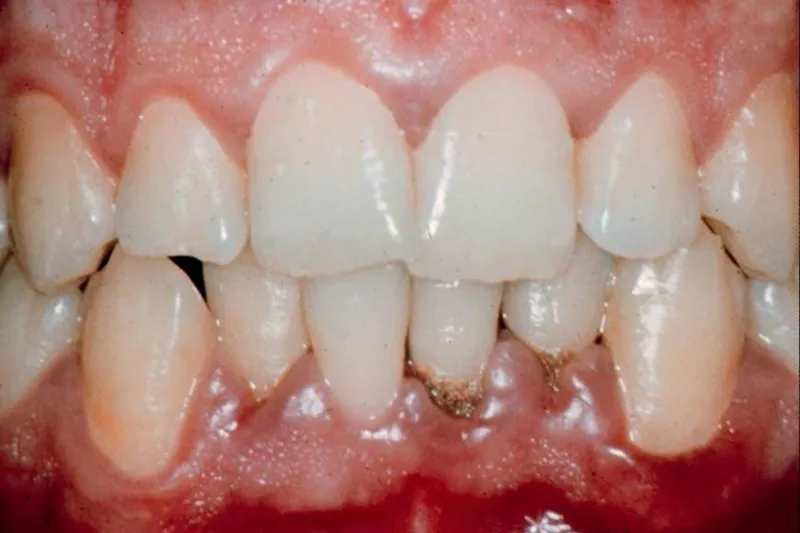

Årsagen til parodontitis skal findes i en kombination af mikrobiota, vært og miljø. Denne opfattelse er i dag generelt accepteret. Alligevel foregår størstedelen af al parodontalbehandling ud fra en monokausal sygdomsopfattelse. Som tandlæger er vi vant til at betragte parodontitis som en plakinduceret sygdom, og vores behandling er næsten udelukkende koncentreret om at bekæmpe plakken ved hjælp af professionelle tandrensninger og forbedring af patienternes mundhygiejne. En international forskergruppe slår imidlertid på lederplads i et estimeret videnskabeligt tidsskrift til lyd for, at tiden er inde til endeligt at acceptere konsekvensen af den multikausale baggrund for parodontitis.

En del patienter udvikler ikke sygdommen, selvom de har belægninger på tænderne. Parodontitis opstår først, når plakken kombineres med andre årsagsfaktorer som fx rygning, diabetes eller genetiske forhold.